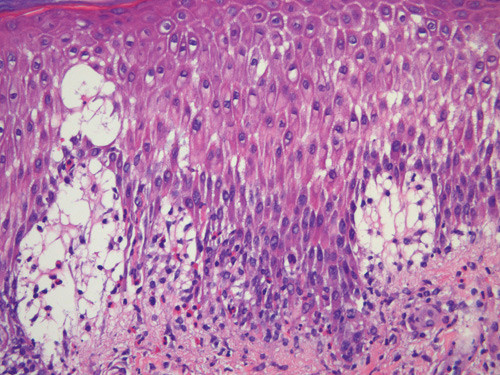

Blodprøver viste senkningsreaksjon 30, CRP 23 mg/l, hemoglobin 12,2 g/100 ml, LPK 12,2 g/l, eosinofile granulocytter 1,4, nøytrofile granulocytter 8,4 og normale verdier for trombocytter, leverenzymer, kreatinin, ANA og immunglobuliner. Det ble ikke påvist IgM- eller IgG-antistoffer mot herpes simplex-virus. Hudbiopsi viste epidermal spongiose, ødem i papillære dermis og perivaskulært betennelsesinfiltrat med et betydelig antall eosinofile granulocytter (fig 3). Immunfluorescens viste lineært nedslag av C3 og IgG i basalmembransonen (fig 4).

Patogenesen ved svangerskapspemfigoid er bare delvis kartlagt. Det er en klar genetisk assosiasjon til HLA-DR3 samt DR4 hos mødre og til HLA-DR2 hos fedre (6). Ved indirekte immunfluorescens kan det påvises sirkulerende IgG-autoantistoffer, hovedsakelig rettet mot det ekstracellulære NC16A-domenet på det transmembrane hemidesmosomglykoproteinet BP180 i hudens basalmembran (7). De samme autoantistoffene binder seg til amnions basalmembran i placenta. En teori er at autoantistoffer rettet mot placentaantigener av paternell haplotype kryssreagerer med hud (8). Det er hevdet at serumnivået av autoantistoffer mot BP180 er korrelert med sykdomsaktiviteten (9). Binding av IgG-autoantistoffer til BP180 i basale keratinocytter aktiverer komplementsystemet og fører i neste omgang til lokal inflammasjon med kjemotaksi av granulocytter og skade på basalmembransonen. På den måten dannes subepidermale bullae med eosinofile granulocytter. Andre typiske histologiske funn er perivaskulær betennelse med eosinofili og ødemer i papillære dermis (10). Ved direkte immunfluorescens påvises lineært nedslag av C3 langs basalmembranen og hos 25 % av pasientene IgG-nedslag.